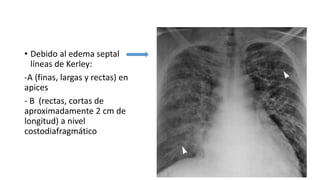

Los signos radiológicos del edema pulmonar incluyen infiltrados intersticiales y alveolares. Estos se producen por un aumento de la presión venosa y la permeabilidad de la membrana alveolo-capilar, lo que causa disnea, taquicardia y otros síntomas. Las líneas de Kerley, el engrosamiento cisural y el signo del manguito son indicativos de edema septal, mientras que las alas de mariposa sugieren el paso de líquido al espacio alveolar.